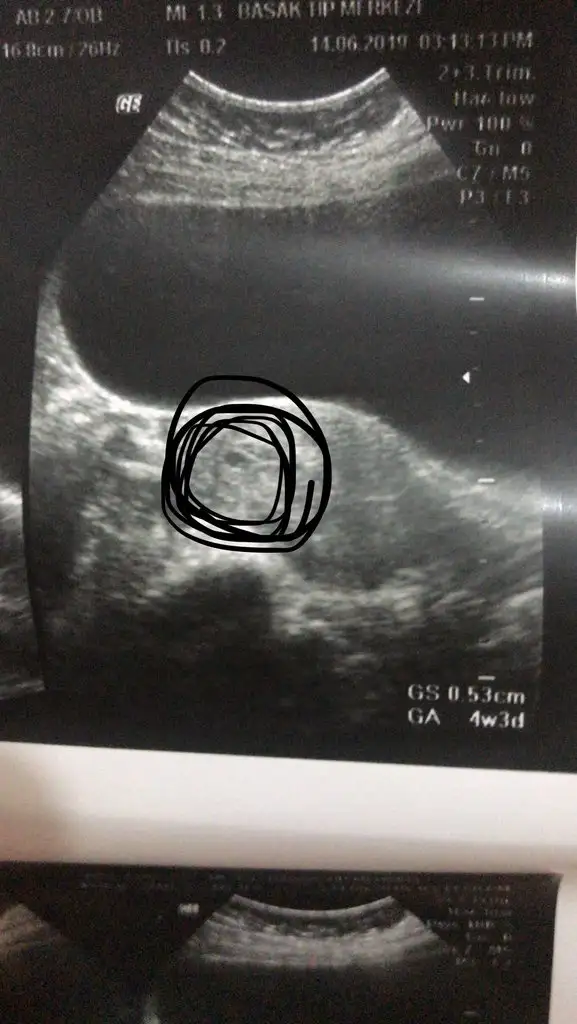

Bunu dün aldım, aslında giderken neredeyse 6 haftalık olmuştur kalbini duyabilirim diye gittim ama 4 yada 4,5 haftalık dedi doktor. Sat 11 Mayıs ve 10 Haziran'da hcg 741 çıkmıştı. Doktor üstten keseyi tam göremediği için alttan baktı ve bunu gördü sadece kalp atışını duyarız belki dedi ama kese içinde birşey görememiş çok mutsuzum şu anda. Birde ilaç kullaniyordum gyno lomexin akıntı vardı ve kaşıntı doktor fazla etki etmez ama ben olsam bunu vermezdim bebek düşünen birine dedi aklım çok karışık bel ağrısından ölüyorum. Doktora söyleyemedim bile ağrımi öyle küçük çıkınca.

Benim ilk 311 di .2 gün sonra 540 . Yuzde 70 artmış yani. O zaman internette okuduklarimla kesin tutunamicak diye üzülmüstüm 4+5 de doktora gittim. 2 gunde bir iki kati olmasi gerek dedi. Karindan gozukmedi. Alttan baktı ufacik gorduk. Doktor bana dedi ki ben alttan da gorceğimizi düşünmemistim. Kan degerlerime bakarak şupheli gebelik olduğunu düşündü yani. Kese görüldüğune göre kan testi yaptirmana gerek yok dedi. O yüzden çok takmayın kafaniza ben baya üzülmustum . Hayirlısıyla sıze tutunacaktır inşAllahBenzer durumdayım biraz yavaş ilerliyor değerim.. ama benim doktorum üç günde bir ikiye katlaması yeterli bizim için diyor.

Seninkinde ufak beyaz bir nokta var bu bile iyi birşey benim ki boşluk ve bel adet sancısı gibi yine de sağol desteğin için..Üzülme kuzum bende 5hafta 2 günlük gittim aynı bu şekilde sadece kese gördüm ve alttan aynı seninki gibi bana da kese kenarda dedi içe doğru büyümesi gerekiyor dedi...yarın doktora gidecem 6hafta 2günlük oluyor bakalım ben görebilecek miyim...bak benimde ultrason görüntün bu şekilde seninkine çok benziyor..

Bende geçen cars gittim sadece kese gorduj cuma gidicem bende inşallah duyarız kalp atışını sağ tarafta ağrı oluyor bende de ve akintim cok fazla hastalandim sanıyorum her zamanEvet canım sat 7 mayıs bende yarın gideceğim ama inan çok korkuyorumbebişg geçen hafta göremedik sadece kese gördük onda da kena da idi çok şükür ki diş gebelik değil ama içe doğru büyümesi gerek çok korkuyorum var mı kuzum kaşık ağırıpg bel ağırıpg bulantı filan..ultrason resmi varsa göndersene